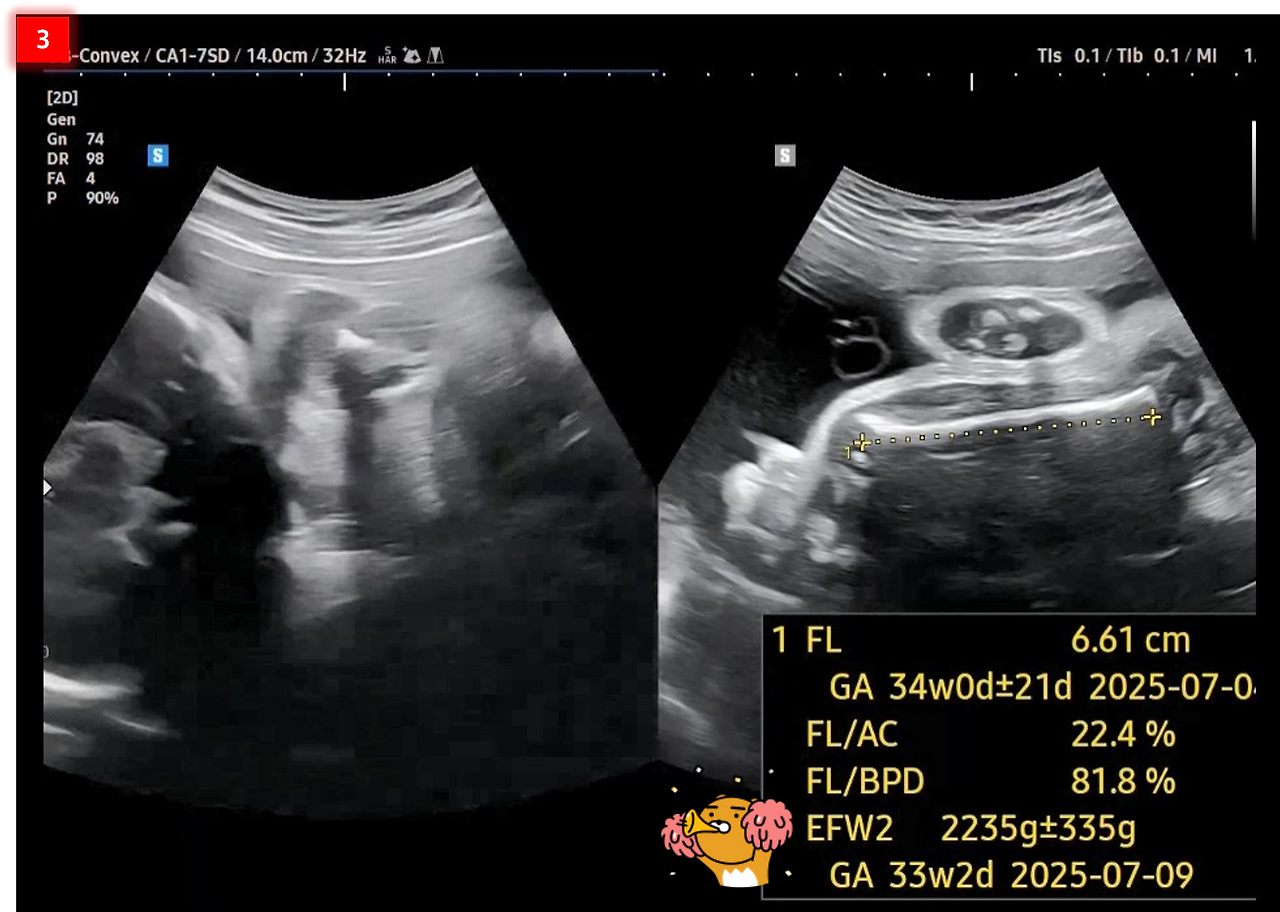

1. 심장박동수(Fetal Heart Rate)는 이번에도 146 bpm입니다. 이 시기의 태아의 정상적인 심장박동수는 120~160 bpm이라고 하네요.

FHR.png [태아 심장박동수 FHR]